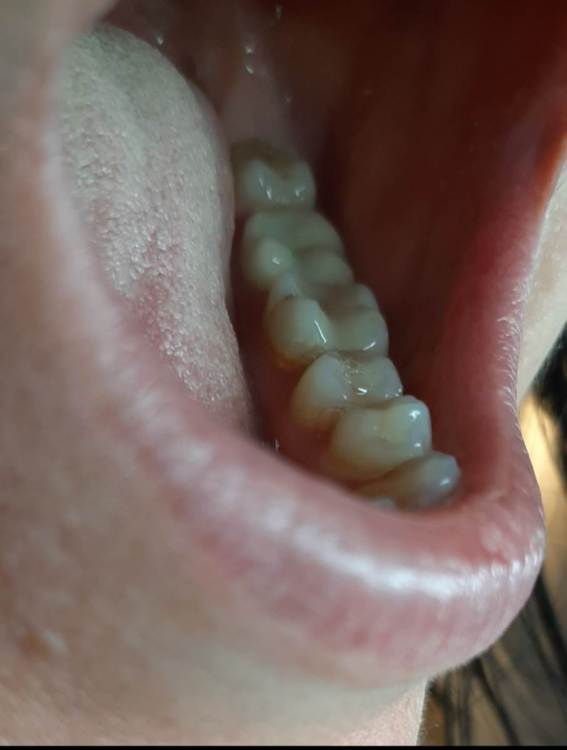

Лана-Лана Опубликовано 6 декабря, 2021 Поделиться Опубликовано 6 декабря, 2021 (изменено) Добрый день. Установили цирконевую коронку на нижнюю семёрку, при примерке я заметила что коронка низкая , но врач убедила что все впорядке типа мой зуб такой и был, самый последний бугор на контакте с восмым зубом с язычной стороны чуть ли не на уровне десны. Теперь когда жуешь и туда попадает что то твердое мясо, яблоко очень больно десну .. я сказала об этом ортопеду но она говорит что по другому не сделать, и предлагает вырвать восьмёрку и засчет этого опустится десна, но это же не выход , да и не хочу я ее удалять, раньше у меня с моим натуральным зубом таких проблем не было.... посмотрите пожалуйста снимки зуба до и фото после, действительно ли у меня был такой низкий зуб? Или это портак? На фото во рту видно что он ниже восьмёрки а край с язычной стороны ещё ниже...и если это плохо сделанно? Можно ли просить переделки ведь он ещё на гарантии? Или это проблемно снять? И что вообще в таких случаях делать если ортопед отказывает в переделке? Писать претензию? Изменено 6 декабря, 2021 пользователем Лана-Лана Ссылка на комментарий